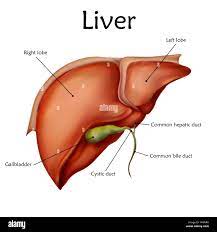

LIVER:

The liver is the most important organ of the metabolic system. It helps convert nutrients into usable substances, detoxifies certain substances, and filters blood coming from the digestive tract through a vein before it joins venous blood flow from other parts of the body. Oxygenated blood reaches the liver via an artery.

The majority of liver mass is in the upper right side of the abdomen, just under the rib cage.

The liver plays many roles in digestion and filtering the blood, including:

producing bile

helping the body filter out toxic substances, including alcohol, drugs, and harmful metabolites

regulating blood levels of various important chemicals, including amino acids

making cholesterol

removing some bacteria from the blood

making some immune factors

clearing bilirubin from the blood

regulating the process of blood clotting, so that a person does not bleed too much and does not develop dangerous blood clotsThe liver partners with the gallbladder to deliver bile to the small intestine. The liver pours bile into the gallbladder, which then stores and later releases the bile when the body needs it to help with digestion.